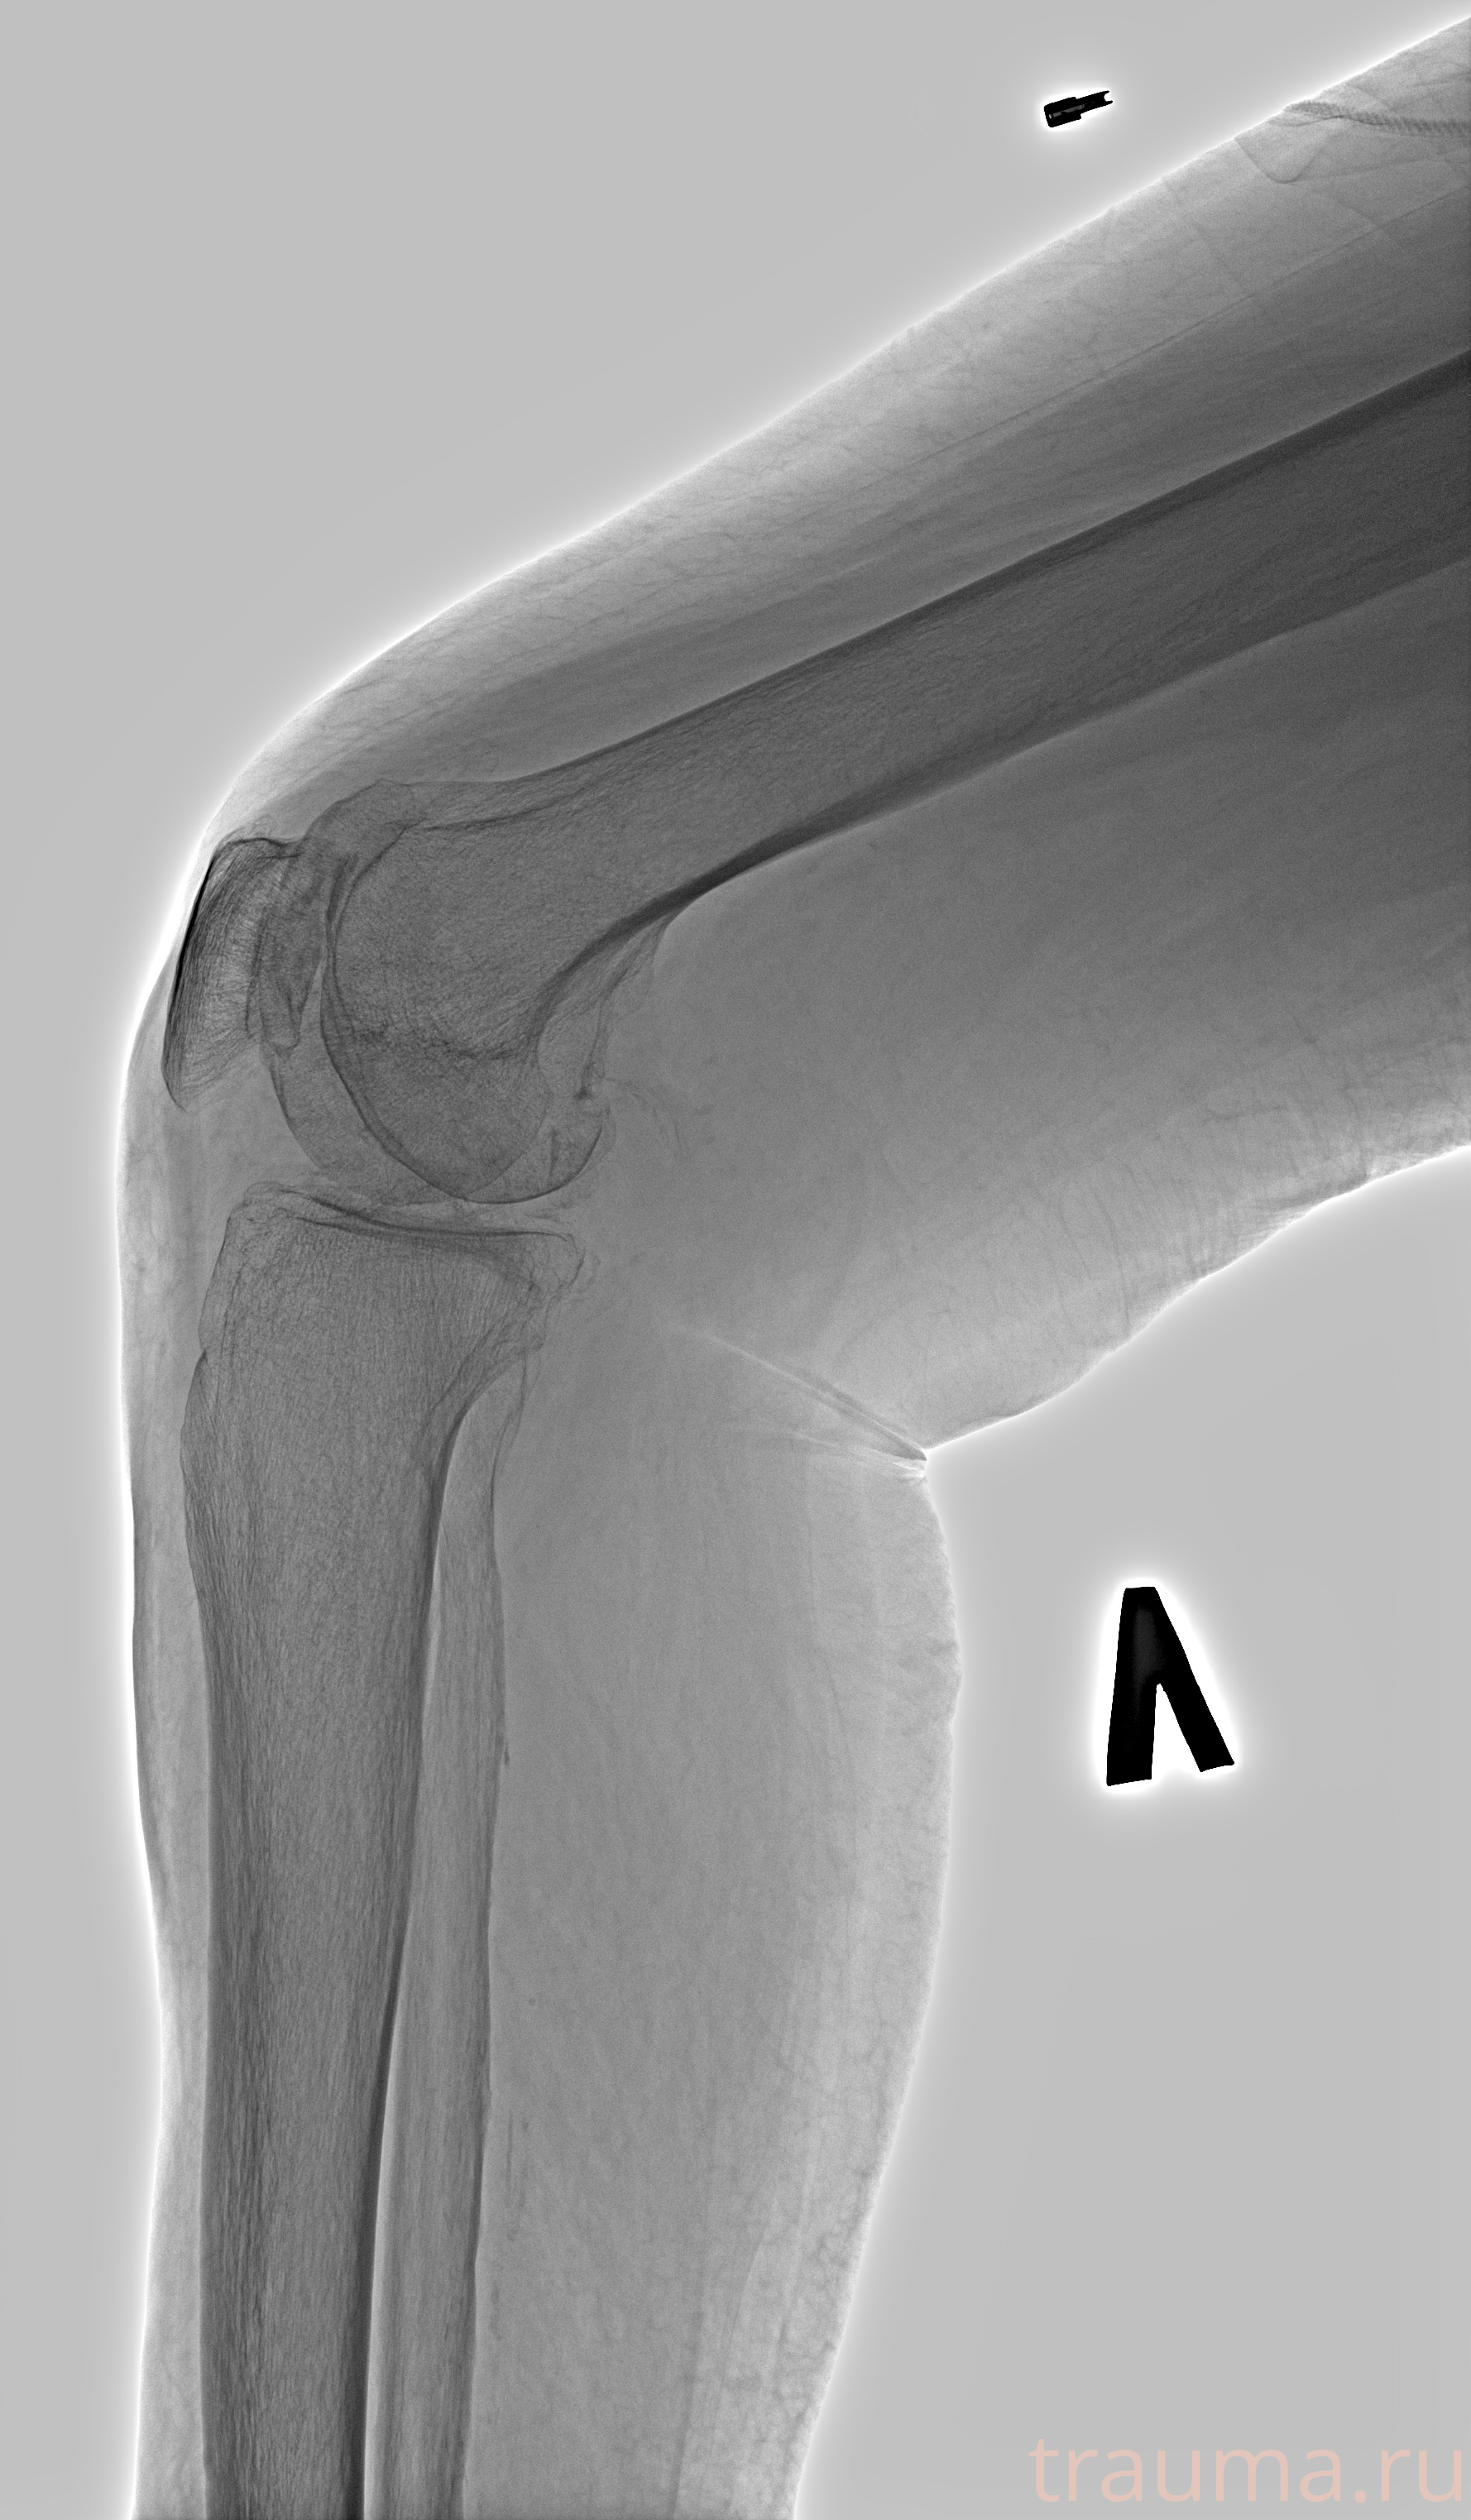

Рентгенограммы